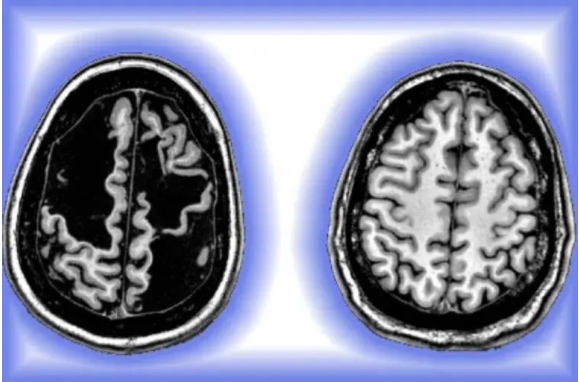

丹尼尔的MRI扫描显示,婴儿时期的严重中风导致他的大脑两侧受伤。与思考、情感、记忆和高级功能有关的大脑区域中,大量组织明显丧失。然而,丹尼尔似乎并没有出现认知、记忆或情感方面的问题。在两个大脑半球中,运动相关区域也有不对称损伤,这会影响运动和平衡等技能。通常,大多中风都会损伤大脑一侧,而双侧损伤带来的后果会更严重。

将丹尼尔的大脑成像数据与其他年轻人的结果进行比较发现,“丹尼尔大脑结构的一部分消失了,他几乎缺了四分之一的大脑皮质(cortex)。”

丹尼尔(左)和尼科博士(右)的大脑影像。丹尼尔大脑影像的暗区反映了左右大脑半球大量组织缺失

影像学检查还显示,在丹尼尔大脑中,坏死组织形成的空隙里充满脑脊液,脑脊液可以缓冲保护大脑免受伤害,同时还可以将营养物质输送到组织中并清除代谢废物。神经元也重新“连接”,促进了大脑功能的保持,从健康组织附近开始,损伤后的“剩余”组织间都逐渐恢复了互相连接。